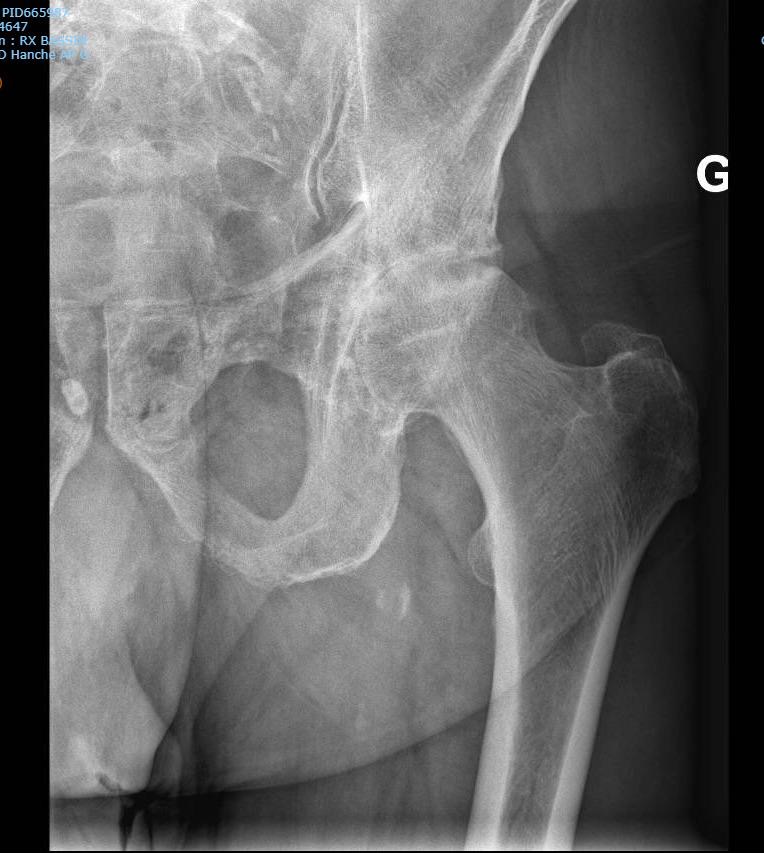

Complex fracture treatment involves the surgical repair of severely broken or misaligned bones using advanced techniques such as internal fixation with plates, screws, or rods. Dr. Enrique Vélez specializes in restoring bone alignment, stability, and function to ensure proper healing and long-term mobility, especially in trauma-related or multi-fragment fractures.

A complex fracture involves multiple bone fragments, displacement, or damage to surrounding tissue, often resulting from high-impact trauma such as accidents or falls.

Treatment usually involves surgery using plates, screws, or rods to realign and stabilize the bone. Dr. Vélez evaluates each case individually to determine the best approach for healing and recovery.